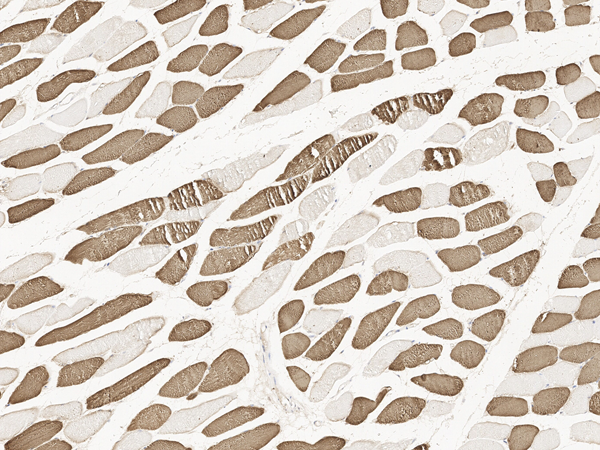

IHC (Immunohiostchemistry)

(Immunochemical staining of human Troponin C in human muscle with rabbit polyclonal antibody at 1:500 dilution, formalin-fixed paraffin embedded sections.)